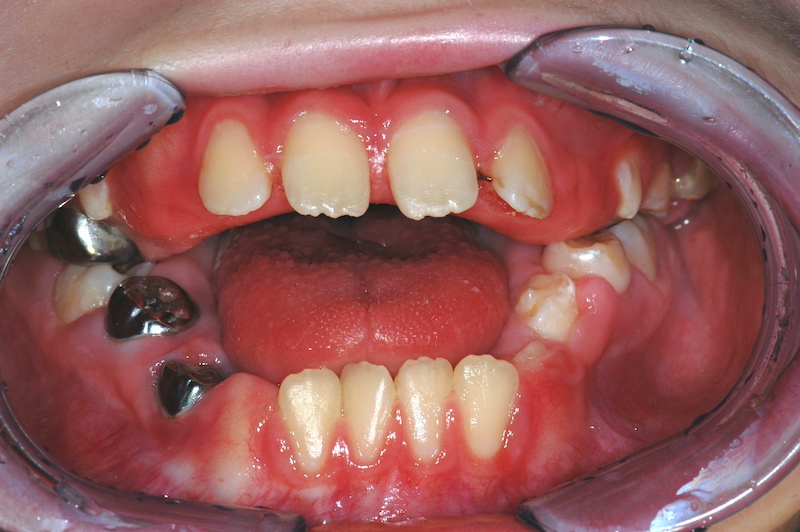

© Prof. A. Rahman

Die sichere Durchführung zahnärztlicher Narkosen bei Kindern erfordert eine enge interdisziplinäre Zusammenarbeit, individuelle Risikobewertung, angepasste Anästhesie- und Überwachungsstrategien sowie eine klare postoperative Nachsorge. Checklisten können dabei helfen, Risiken zu minimieren und die zahnärztliche Versorgung kindgerecht fortzuführen. In dem Webinar wird ein Überblick über die zentralen Aspekte technischer Standards wie Monitoring, sichere Vorbereitung, Medikamente, sowie medizinische Aspekte bei Allgemeinerkrankungen mit klinischen Fällen vorgestellt.